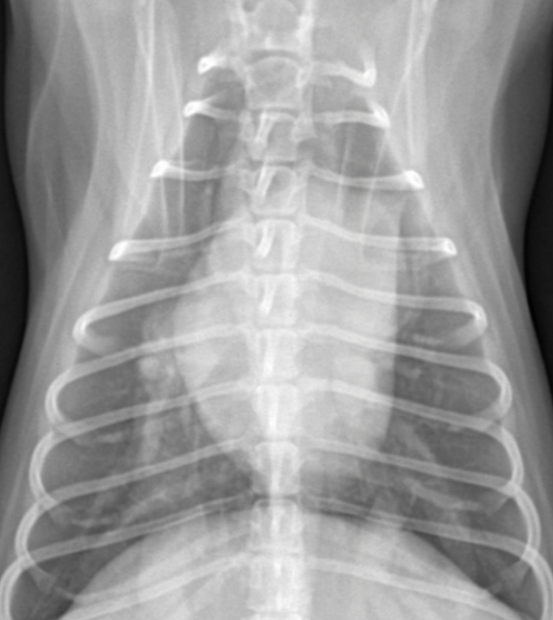

| Microcardia |

|---|

| ICS < 2.5 |

| Hypovolemia, shock, dehydration, Addisonโs dz, Canine hypoadrenocorticism ๋ฑ |

![]() |